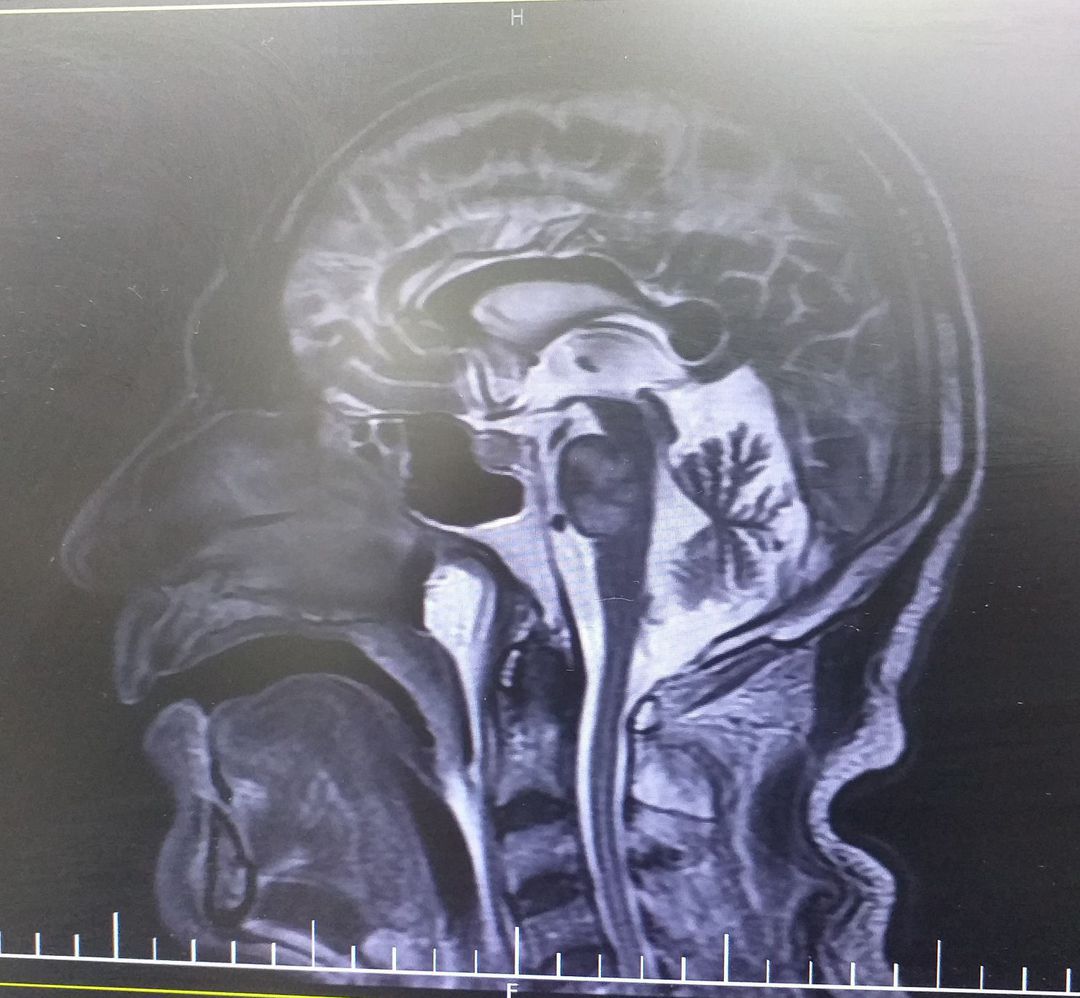

MRI dx?

Locked in syndrome